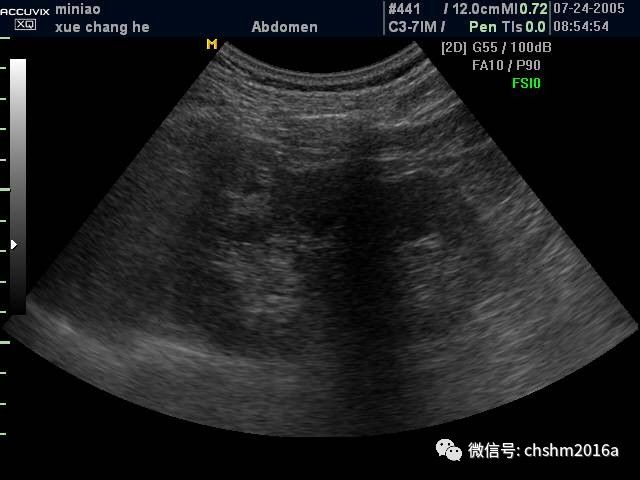

肾肿瘤超声鉴别诊断

肾肿瘤彩超,肾肿瘤ct

肾肿瘤